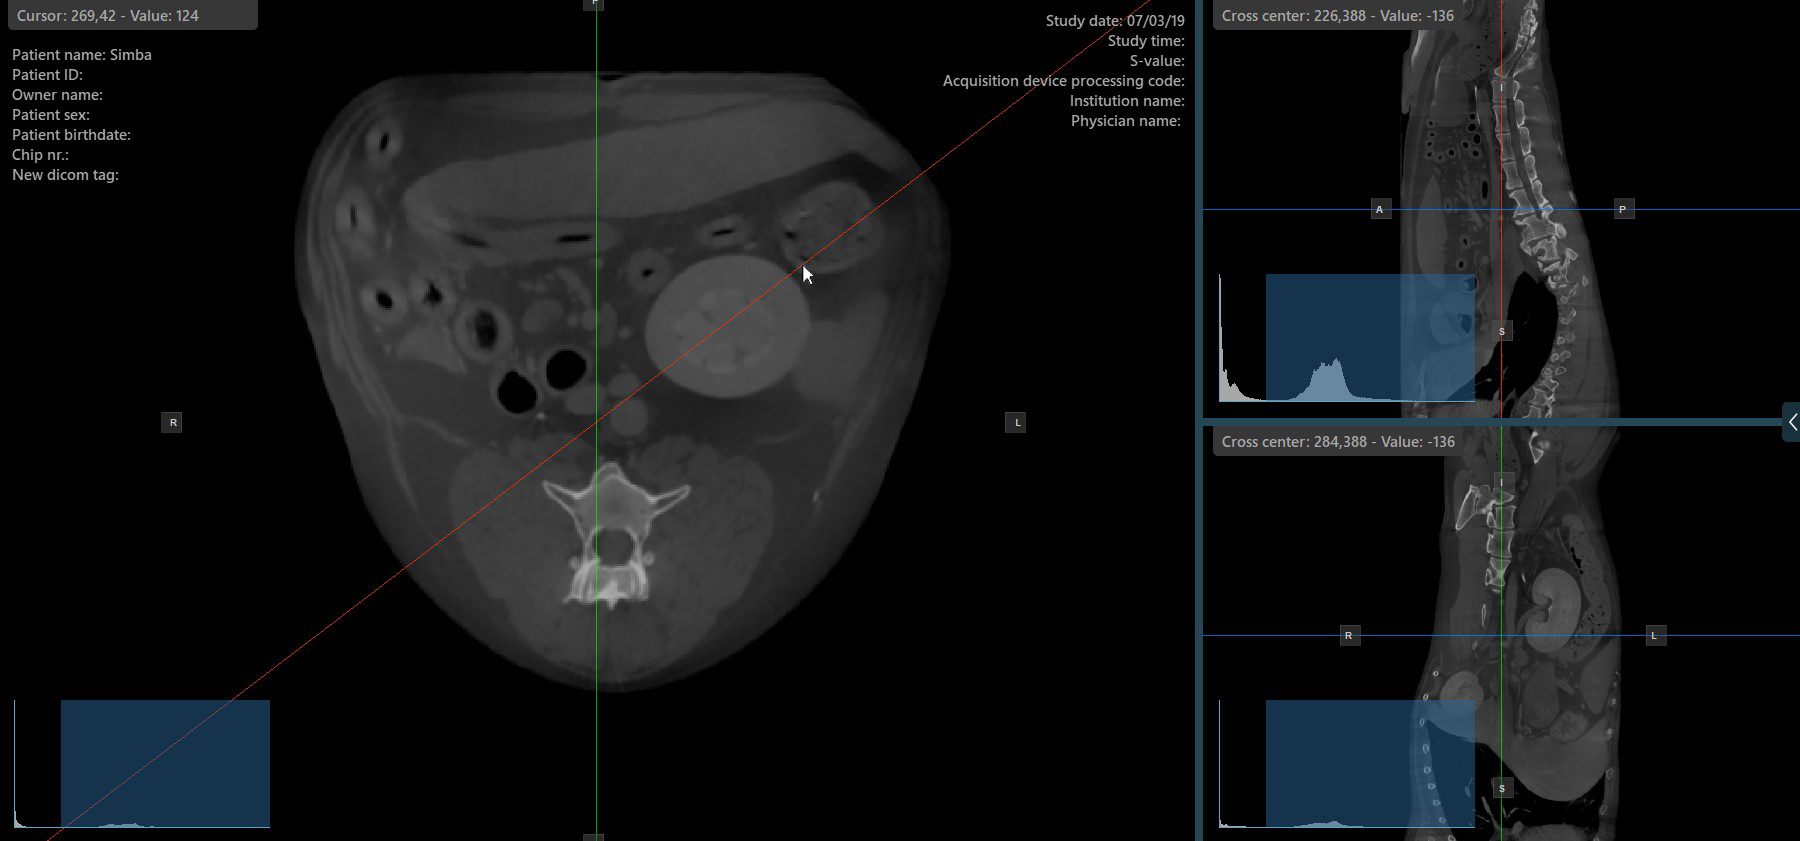

Altering the rotation of a slicer will change the orientation of the corresponding image planes. Individual slicers can be selected by using the Select Item (Default) tool, assigned to the right mouse button by default.

Once the specific slicer is selected, drag the slicer in the desired direction to rotate it. The corresponding image plane’s orientation changes accordingly.

By default, each slicer can be rotated separately. The corresponding icon in the left toolbar of the CT Viewer will be deselected when the slicers are rotated individually.

Press the Perpendicular Slicers icon in the left toolbar to activate simultaneous rotation of the slicers. Regardless of their previous orientation, the slicers are repositioned to be perpendicular to each other.

Toggle the Perpendicular Slicers option to switch the active mode of the slicers at any time, or choose one of the Tools -> Perpendicular Slicers or Tools -> Separate Slicers options from the CT Viewer menu.